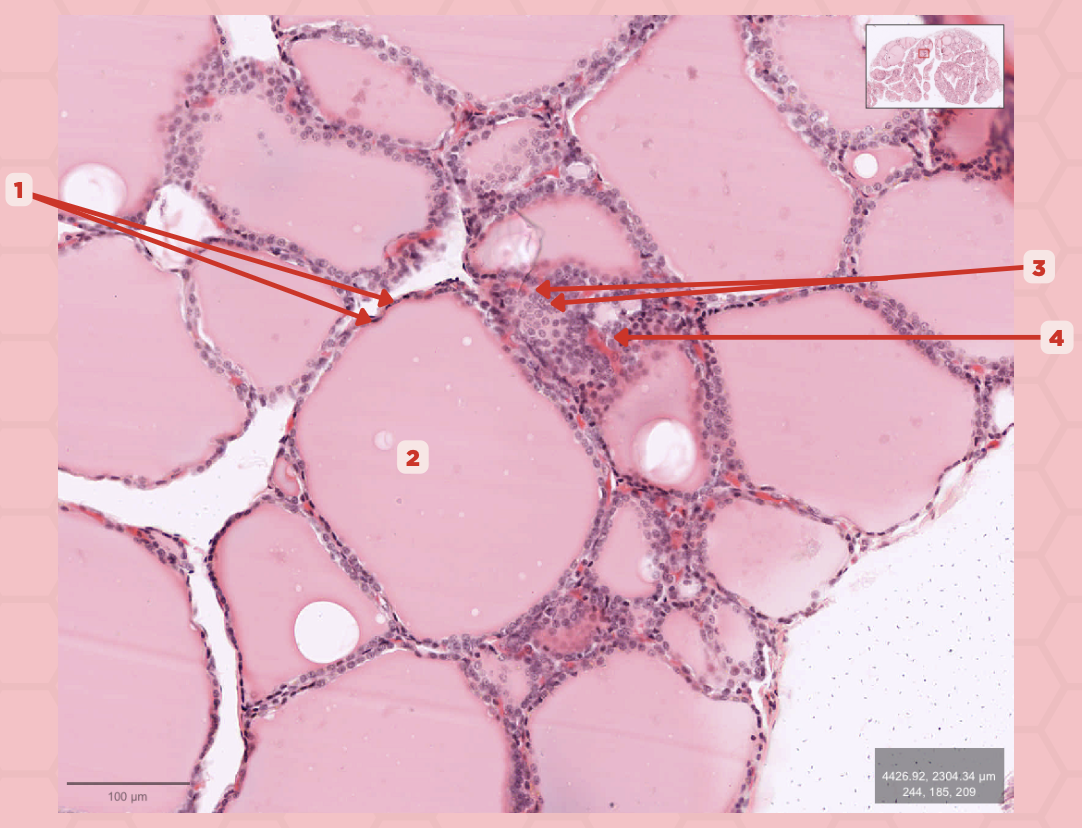

Thyroid

Identify the specimen.

Lobules

Identify the structure labeled as 1.

Follicles

Identify the structure labeled as 2.

T3 and T4 Hormone

What type of hormone is being secreted by the pointer #1?

Follicular Cells

Identify the structure labeled as 1.

Colloid

Identify the structure labeled as 2.

Parafollicular Cells

Identify the structure labeled as 3.

Capillary

Identify the structure labeled as 4.